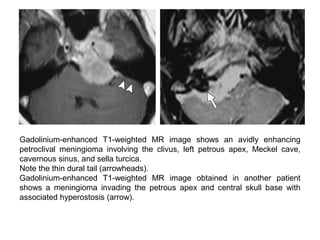

Gadolinium-enhanced T1-weighted MR image shows an avidly enhancing

petroclival meningioma involving the clivus, left petrous apex, Meckel cave,

cavernous sinus, and sella turcica.

Note the thin dural tail (arrowheads).

Gadolinium-enhanced T1-weighted MR image obtained in another patient

shows a meningioma invading the petrous apex and central skull base with

associated hyperostosis (arrow).